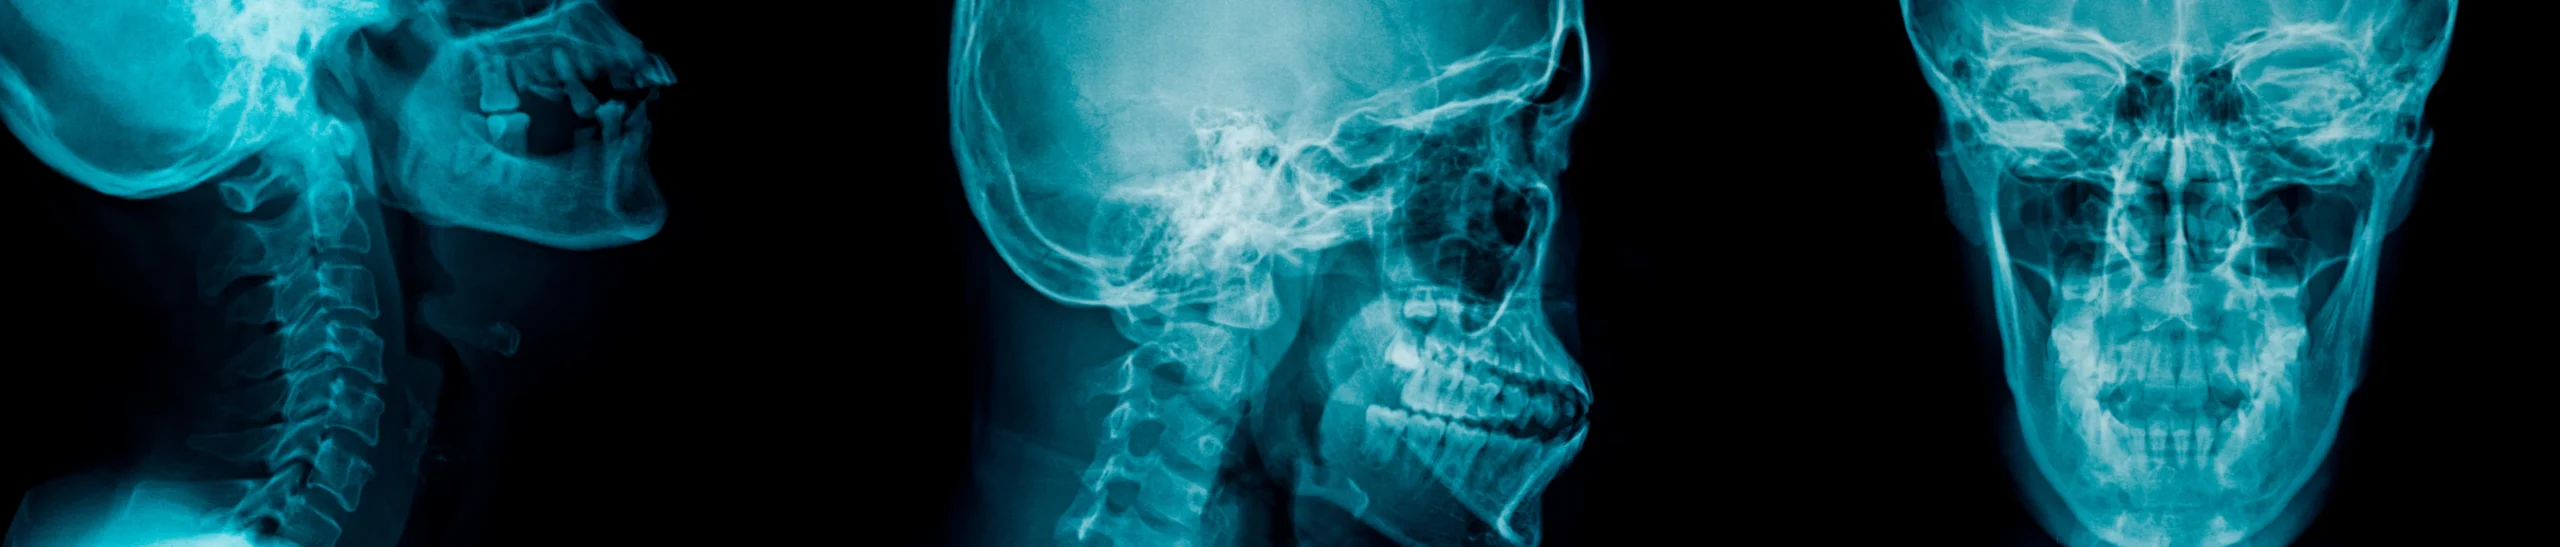

- Examens complémentaires

Des radiographies ou des photographies peuvent être nécessaires pour évaluer la position des racines et la structure osseuse. Dans certains cas, une empreinte ou un scan 3D des arcades dentaires permet de visualiser précisément la situation.